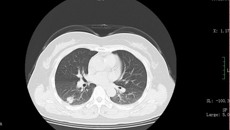

电视胸腔镜手术(Video-Assisted Thoracic Surgery,VATS) 被视为二十世纪胸部外科革命性的一大突破,在胸外疾病诊断、治疗中应用范围广,几乎囊括了胸外科各种疾病的检查和治疗;其中全胸腔镜肺叶切除术代表了胸腔镜技术的制高点,是胸部微创外科皇冠上的一颗明珠。日前,一附院外七科在成功开展近百例胸腔镜微创胸部疾病手术的基础上,又成功完成全胸腔镜下肺叶切除+纵隔淋巴结清扫术,患者现已经康复出院。该手术的成功标志...05.172013